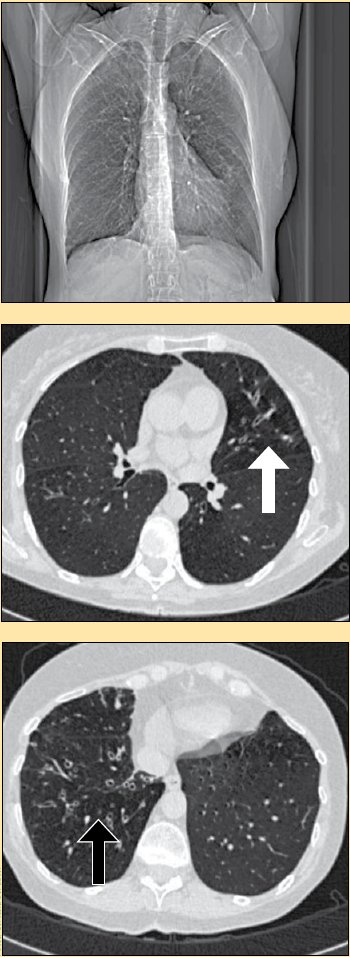

Se le realizó una radiografía de tórax donde no se observaron alteraciones pleuropulmonares y lo mismo ocurrió en la radiografía de senos paranasales. Se le realizó estudio endoscópico donde no se informó alteraciones de la mucosa gástrica. En la prueba funcional, se informó un trastorno obstructivo de intensidad leve con respuesta significativa al broncodilatador. Con estos datos, se realizó una tomografía de pulmón donde se notaron múltiples bronquiectasias en los segmentos lingulares del pulmón izquierdo y en los lóbulos medio e inferior del derecho. Se realizó una broncoscopia donde se informa secreciones bronquiales blanco-amarillentas en ambos árboles bronquiales y se realizó lavado bronquial. Los exámenes de laboratorio clínico se muestran en la tabla 1 .

Desde que se realizaron los estudios y que no hubo evidencia de las entidades más frecuentes, se decidió realizar una tomografía de pulmón que hizo evidente las múltiples bronquiectasias en la língula y los lóbulos medio e inferior del pulmón derecho. Se sospechó entonces que pudiera tratarse de una enfermedad producida por un germen atípico, por lo que se realizó una broncoscopia, y así poder llegar al diagnóstico de un complejo Mycobacterium avium-intracellulare, lo que llevó a concluir que la causa de la tos era el síndrome de Lady Windermere. En este caso se presenta una rara causa de tos crónica, la que con el empleo adecuado del método clínico y de los medios de diagnóstico adecuados, pueden establecer el diagnóstico y en consecuencia el tratamiento adecuado.